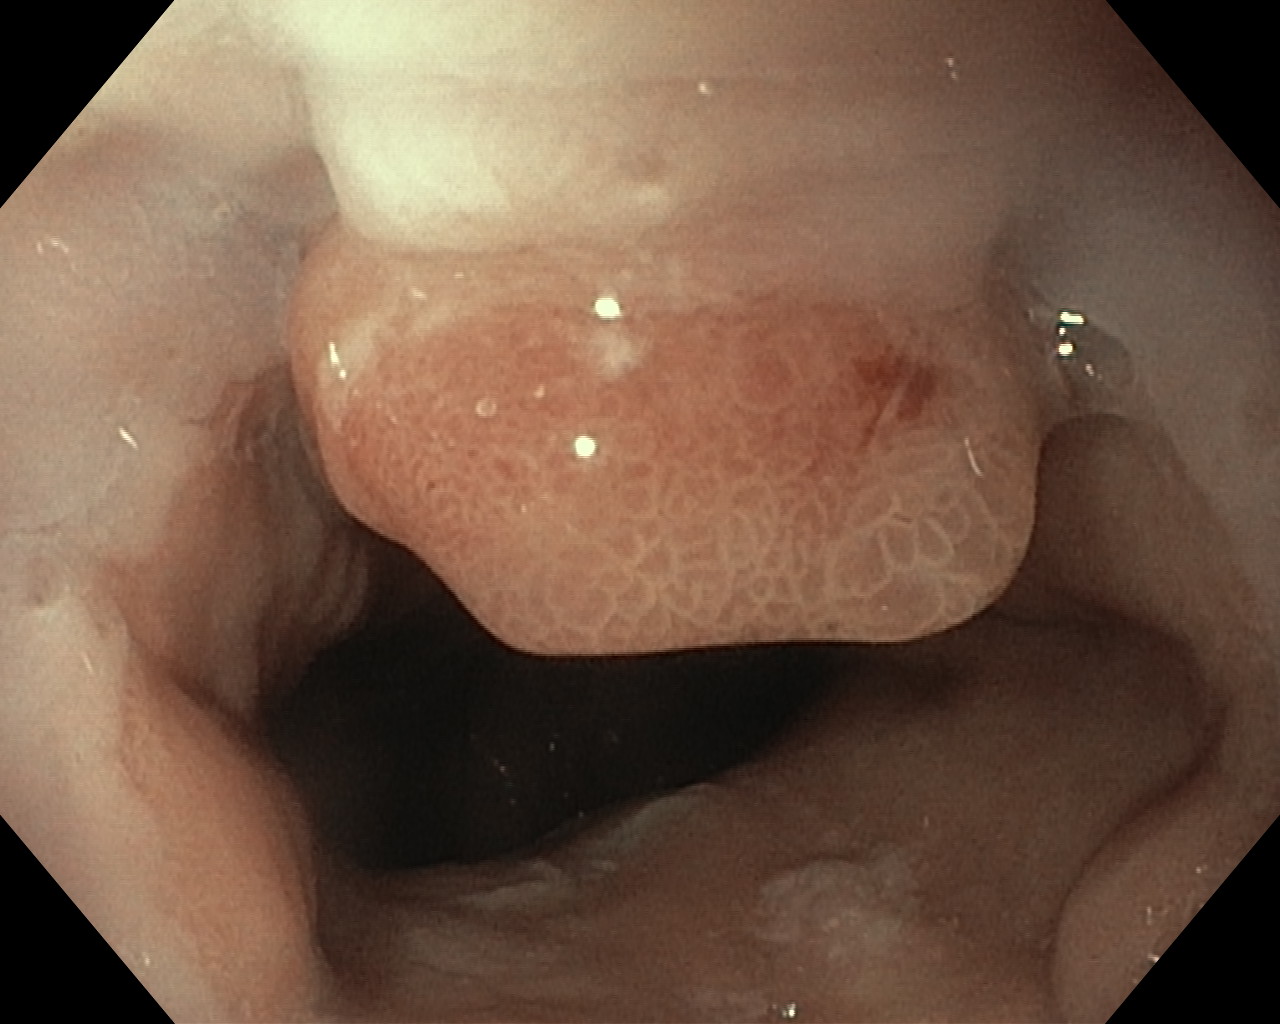

Polipy